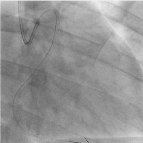

As the first attempt, we used TREK balloon 2.5 × 15 mm anchored in the second run through wire placed in left anterior descending artery (Figure 7) and tried to extract the broken tip. Failed to retrieve with the anchoring balloon technique. The second run through wire was advanced across the LCx and positioned in the distal LCx, twisting parallel wire technique was tried (Figure 8). The broken tip was moving along with the guide wire freely from proximal to distal LCx but failed to pass from the very proximal and ostial LCx. Planned to engulf by using guide catheter extension, Guidezilla (Boston Scientific, USA) has not even failed but resulting in dislodgement further down to distal LCx (Figure 9). Further attempt to trap with low profile TREK 3.0 × 15 mm by positioning beyond the tip, inflating upto 6 atm pressure (Figure 10) also not working well in retrieving the broken tip. By using various techniques including twisting parallel wire technique, using low profile balloon on another parallel guidewire, reaching out to the tip by using guide catheter extension, Guidezilla (Boston Scientific, USA) has failed and leaving the last option as catching with the snare. The first attempt to snare with 10mm × 120cm snare only dislodged the broken tip more distally. The second snare device 4mm × 200cm Goose Neck Amplatz Microsnare finally managed to capture the guidewire distal to the broken tip (Figure 11) and the whole system was retrieved successfully (Figure 12,13). POBA along LCx was done by using 3.0 × 15 mm and upsize to 5.0 × 15 mm balloon. Final angiogram revealed flow in the LCx was re-established (TIMI II flow) with no major dissection or perforation was identified (Figure 14). In view of established flow within the ectatic coronary and improving chest pain, we didn’t proceed with stenting. The patient was discharged uneventfully after completing 5 days of low molecular weight heparin and discharged with dual antiplatelet therapy, Aspirin and Plavix and non-vitamin K antagonist oral anticoagulant (NOAC). The patient was reviewed 3 months and 6 months duration, he was asymptomatic with echocardiogram showing left ventricular ejection fraction of 65% with no regional wall motion abnormality.

Figure 11. Snaring with Amplatz goose neck